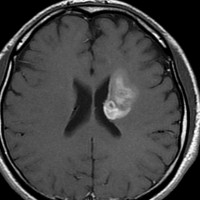

放射線治療後7週目

フレア画像です。腫瘍サイズが増大しています。もともと腫瘍周辺浮腫はなかったのですが大脳基底核と視床に浮腫が出現しています。スード・プログレッションの始まりです。